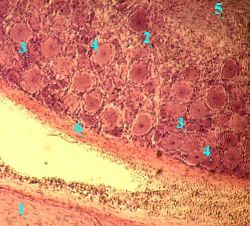

В. Характеристика чувствительных нейроцитов

а) Чувствительные нейроциты спинномозговых (да и прочих чувствительных) узлов являются

псевдоуниполярными.

Это значит, что

места отхождения аксона и дендрита от тела клетки близки,

и кажется, будто клетка имеет всего один отросток,

который затем Т-образно делится на два.

б) Но разглядеть место отхождения отростков от тела чувствительного нейрона на обычном препарате обычно не удаётся.

в) Так что даже при большом увеличении у этих нейронов можно видеть лишь

крупное округлое тело (7)

а в центре последнего - относительно небольшое ядро (8) с плотным ядрышком.

Г. Клетки, окружающие нейроциты

Вокруг тела каждого нейрона последовательно располагаются:

клетки-сателлиты (9), или глиоциты ганглиев, или мантийные глиоциты - с мелкими овальными ядрами,

базальная мембрана,

соединительнотканная капсула (10); образующие её фибробласты отличаются узкими ядрами.

То же видно и здесь:

часть тела (1) чувствительного нейрона;

клетки-сателлиты (2) и

фибробласты (3).